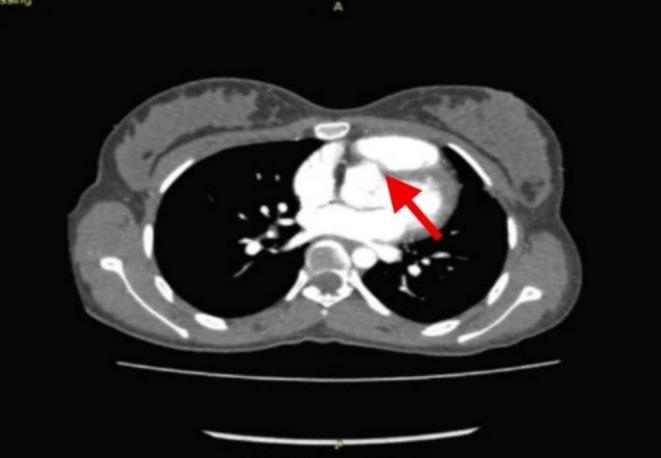

An aorto-cameral fistula (ACF) is a rare abnormal communication between the aorta and a cardiac chamber, often resulting from trauma, ruptured sinus of Valsalva aneurysms, infective endocarditis, aortic dissection, or iatrogenic causes. Clinical presentations vary from asymptomatic cases to severe hemodynamic compromise, including heart failure, arrhythmias, and sudden cardiac death. We present a 17-year-old female with exertional dyspnea and fatigue, 9 years after a penetrating chest trauma. Transthoracic echocardiography and cardiac CT revealed an 8 mm fistulous connection between the right sinus of Valsalva and the right ventricular outflow tract. Surgical repair under cardiopulmonary bypass successfully closed the defect with 5-0 Prolene sutures, confirmed intraoperatively without residual shunting or aortic valve dysfunction. The patient recovered uneventfully and was discharged on postoperative day four. This case highlights the diagnostic challenges of chronic traumatic ACF and emphasizes the importance of multimodal imaging for early detection and timely surgical intervention to prevent long-term hemodynamic deterioration. Given the potential for delayed complications, clinicians should maintain a high index of suspicion for post-traumatic cardiac fistulas, even years after the initial injury.

主动脉-心腔瘘(ACF)是一种罕见的主动脉与心腔之间的异常连通,通常由外伤、瓦氏窦瘤破裂、感染性心内膜炎、主动脉夹层或医源性原因引起。临床表现从无症状到严重的血流动力学障碍不等,包括心力衰竭、心律失常和心源性猝死。我们报告一例17岁女性,在胸部穿透伤9年后出现劳力性呼吸困难和疲劳。经胸超声心动图和心脏CT显示,瓦氏窦右窦与右心室流出道之间存在一个8毫米的瘘管连接。在体外循环下进行手术修复,成功地用5-0普罗林缝线闭合了缺损,术中证实无残余分流或主动脉瓣功能障碍。患者恢复顺利,术后第四天出院。该病例突出了慢性创伤性ACF的诊断挑战,并强调了多模态成像对于早期检测和及时手术干预以防止长期血流动力学恶化的重要性。鉴于可能出现延迟并发症,临床医生即使在初始损伤多年后,也应高度怀疑创伤后心脏瘘。